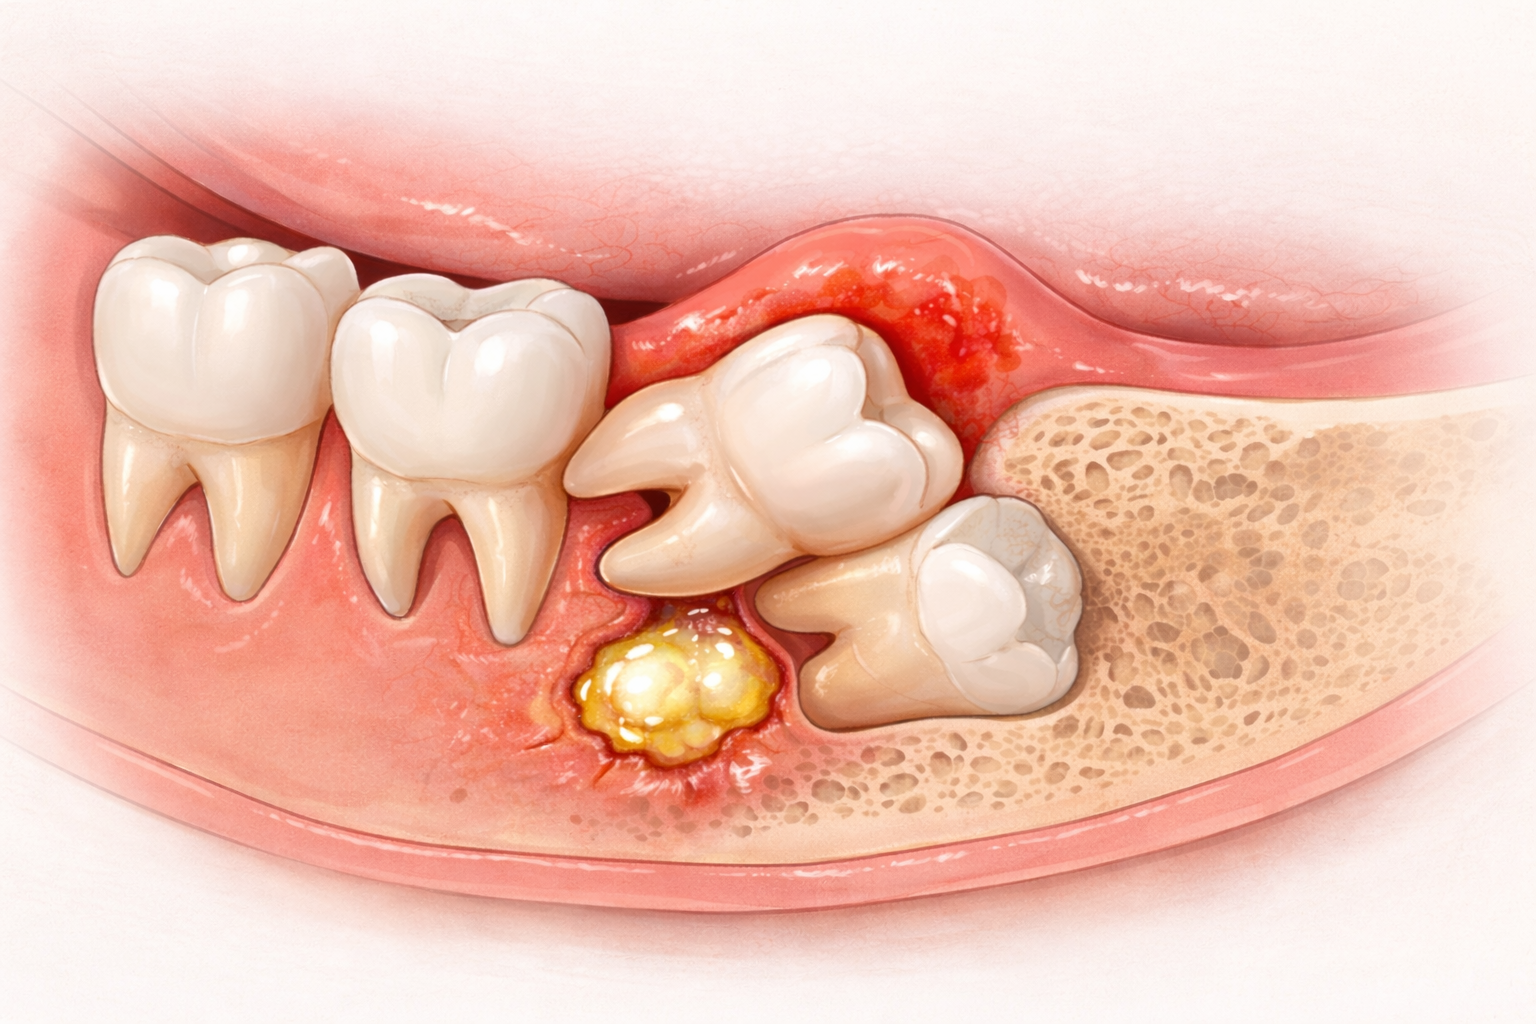

Ilustrasi Gigi Bungsu (Impaksi). (Foto: Dok. RS Syarif Hidayatullah)

Ilustrasi Gigi Bungsu (Impaksi). (Foto: Dok. RS Syarif Hidayatullah)

Apa Itu Impaksi Gigi Bungsu secara Medis?

Secara klinis, impaksi didefinisikan sebagai kegagalan gigi untuk tumbuh sepenuhnya ke posisi fungsional yang benar pada waktunya, karena terhalang oleh hambatan fisik berupa gigi tetangga, jaringan gusi yang padat, atau tulang rahang yang tebal.

Berdasarkan tingkat keparahannya, impaksi dibagi menjadi dua kategori besar:

- Impaksi Jaringan Lunak (Soft Tissue Impaction): Mahkota gigi telah menembus tulang namun masih tertutup oleh jaringan gusi.

- Impaksi Tulang (Bone Impaction): Gigi masih sepenuhnya atau sebagian tertanam di dalam tulang rahang. Kondisi ini biasanya memerlukan prosedur bedah yang lebih kompleks.

Klasifikasi Posisi Impaksi: Bagaimana Gigi Anda Tumbuh?

Dokter spesialis bedah mulut di Rumah Sakit Syarif Hidayatullah menggunakan klasifikasi khusus untuk menentukan tingkat kesulitan operasi, di antaranya:

- Mesioangular (Mesial): Gigi miring ke arah depan, menekan gigi geraham kedua. Ini adalah jenis yang paling sering memicu kerusakan gigi tetangga.

- Distoangular (Distal): Gigi miring ke arah belakang, sering kali menyebabkan nyeri yang menjalar ke arah telinga atau sendi rahang (TMJ).

- Horizontal: Gigi tumbuh mendatar seolah-olah sedang "tidur" di dalam tulang rahang. Tekanan yang diberikan jenis ini sangat besar.

- Vertical: Gigi berada pada posisi tegak, namun gagal muncul ke permukaan karena rahang terlalu sempit.

Mengapa Impaksi Harus Segera Ditangani? (Bahaya Komplikasi)

Mengabaikan impaksi gigi bungsu hanya karena rasa nyerinya bersifat hilang-timbul adalah sebuah kesalahan medis. Berikut adalah bahaya yang mengintai jika impaksi dibiarkan tanpa tindakan:

- Perikoronitis (Infeksi Akut): Ini adalah komplikasi paling umum. Sisa makanan terjebak di bawah gusi yang menutupi gigi impaksi (operculum), menjadi sarang bakteri, dan menyebabkan peradangan hebat, nanah (abses), hingga demam.

- Karies dan Kerusakan Gigi Tetangga: Tekanan gigi bungsu dapat merusak enamel gigi geraham kedua di depannya. Karena sulit dibersihkan, kedua gigi tersebut bisa berlubang secara bersamaan.

- Kista dan Resorpsi Tulang: Kantung benih yang membungkus gigi impaksi dapat terisi cairan dan berkembang menjadi kista odontogenik. Kista ini bersifat destruktif; ia dapat menghancurkan tulang rahang di sekitarnya dan mematikan saraf.

- Gangguan Sendi Rahang: Posisi gigi yang miring dapat mengubah cara Anda menggigit (maloklusi), yang pada jangka panjang memicu gangguan sendi rahang dan sakit kepala kronis.